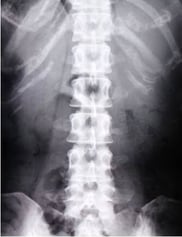

① 腰 痛(66歳・女性)

病院では骨粗鬆症と言われたそうです。投薬とリハビリで幾分回復はしましたが、いまだに長時間歩いたり、立ち続けることが出来ません。

骨粗鬆症は本来、骨の老化と言われています。現代医学において、原因は運動不足、ホルモンバランスの崩れ、カルシウム不足等と言われています。